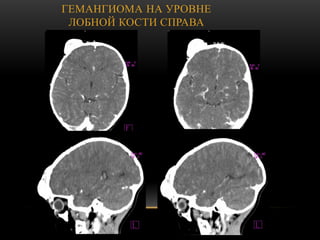

ГЕМАНГИОМА НА УРОВНЕ

ЛОБНОЙ КОСТИ СПРАВА

ГЕМАНГИОМА НА УРОВНЕ ЛОБНОЙ КОСТИ

СПРАВА